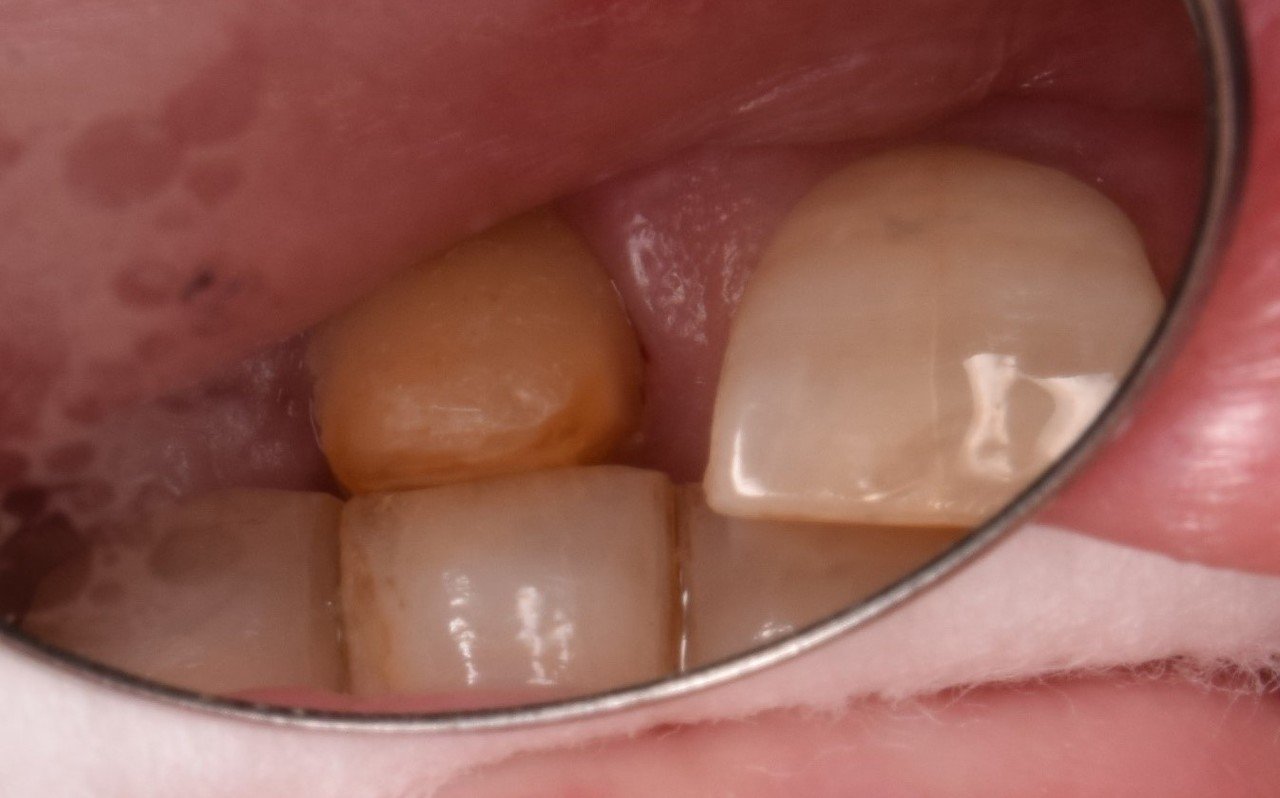

これらですね! 左がインレー、右がクラウンとなるわけです。

これらが外れたら、削った部分が露出されるわけです。

このように修復しているわけですが、象牙質まで切削されており外側のエナメル質より虫歯になりやすいわけですが、それは構造が違うからなのです。